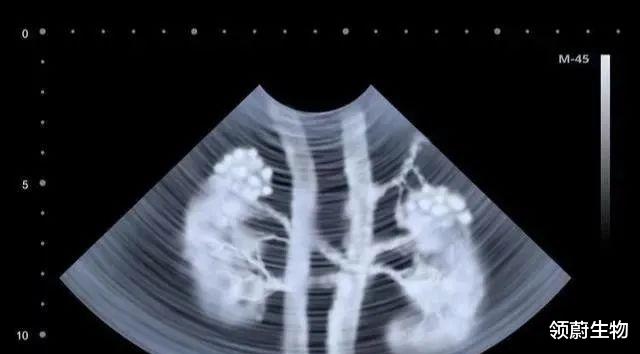

研究显示 , 静脉内注射的MSCs能够迁移到急性和慢性肾损伤模型动物的肾小球、肾间质、小管周围血管和肾小管 。